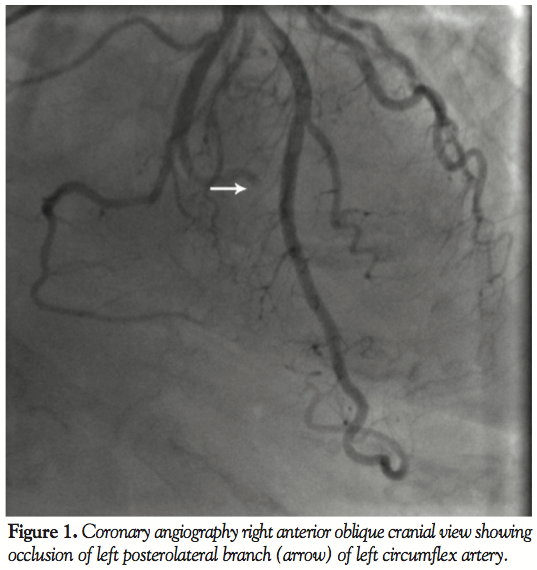

ng/mL), but subsequent tests revealed increased levels of cardiac enzymes (troponin I 5.23 ng/mL, creatinine kinase 59.8 ng/mL, myoglobin 266 ng/mL). Electrocardiogram revealed ST segment elevation in leads II, III, and aVF with reciprocal changes in leads I and aVL. The patient was emergently transferred for catheterization, which revealed 100% stenosis of left posterolateral branch of left circumflex artery (Figures 1 and 2). Other coronary arteries were clean. Percutaneous transluminal

coronary angioplasty was unsuccessful with no improvement of blood flow after first balloon inflation. The lucency in the obstruction with abrupt cut-off, which is an angiographic feature of embolism, pointed to a primary embolic event. The patient became hypoxemic and bedside echocardiography was performed to rule out right ventricular strain due to pulmonary embolus. Echocardiography revealed mild inferolateral hypokinesis and a large, soft-tissue mass partially filling the left atrial cavity with partial obstruction of mitral orifice by a tumor, causing moderate mitral

Discussion. Coronary atherosclerotic disease is the most common pathology leading to myocardial infarction. Other rarer causes include congenital coronary artery anomalies, inflammatory diseases of coronary arteries, dissection of aorta, metabolic disorders, coronary spasm, myocardial contusion, and emboli to coronary artery. These emboli may be paradoxical emboli or originate from cardiac tumors, left heart thrombi, infective endocarditis, or prosthetic valves.1 Our patient presented with acute myocardial infarction due to occlusion of the posterolateral branch of the left circumflex artery. Splenic infarct suggested probable embolic phenomenon. Along with detection of the left atrial sarcoma and angiographic findings, this points to coronary emboli as the most likely cause of myocardial infarction. Hypoxemia in our patient was probably precipitated by tachycardia in the setting of moderate mitral stenosis.